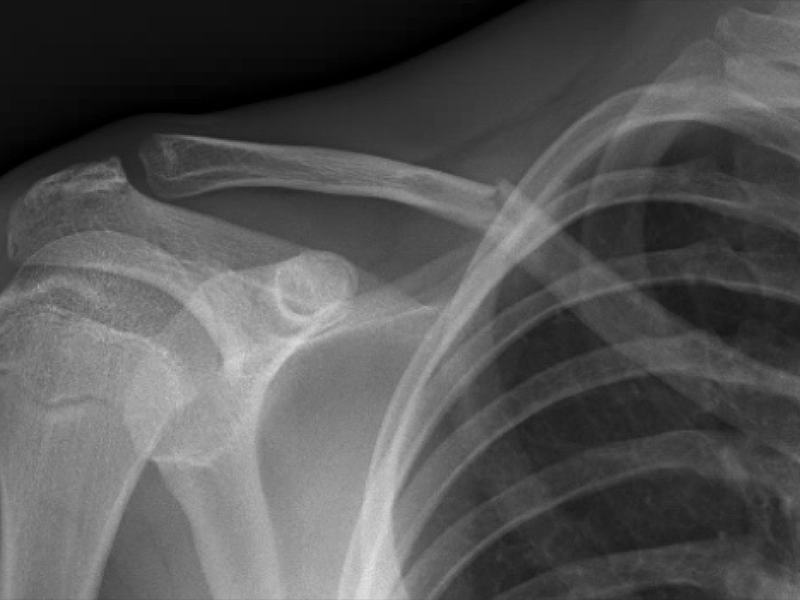

Case 3

Here we see a 17-year-old football player with a shoulder injury. Again, we had the answer before we left the bedside as the displaced fracture is clear on the ultrasound.